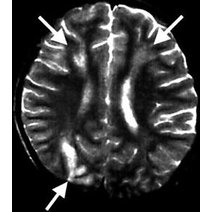

- 格林巴利是一急性或亚急性发作,慢性损害神经根及中枢神经的疾病,起病前1,4周有上呼吸道或消化道感染病史,或有疫苗预防接种史,四季均可发病,夏秋季为多,其病发严重时可侵犯脊髓前角细胞和脑干神经核以及大脑运动皮质锥体细胞危及生命,属免疫性疾病

- 格林巴利综合征病因病因与发病机制目前尚未完全阐明,一般认为与发病前有非特异性感染史与疫苗接种史,而引起的迟发性过敏反应性免疫疾病,其主要病变是周围神经广泛的炎症性节段性脱髓鞘,其临床症状为起病前1,4周有上呼吸道或